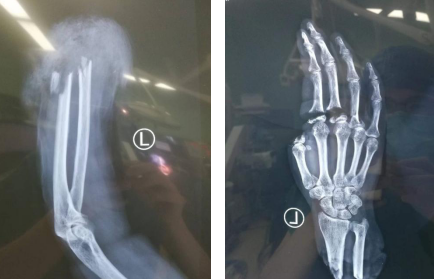

术前X片

术中探查,王女士左前臂自中下三分之一处撕脱性完全离断,创面边缘不齐,且伤口污染严重。在进行仔细的创面清理后,齐伟亚主任与熊祖国医生为其进行了断肢、指再植,本次手术历时12个多小时,手术非常成功。

术后X片